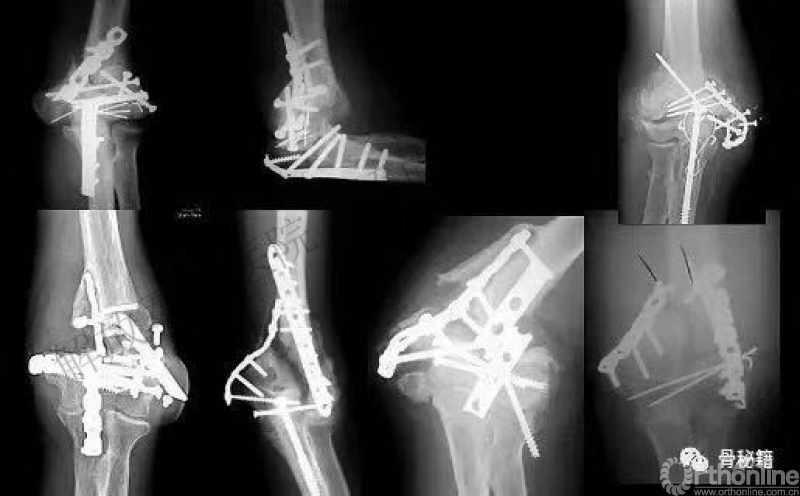

看看这些失败的case,肱骨远端不简单!

然而

AO固定技术流程,会让骨折简单起来!